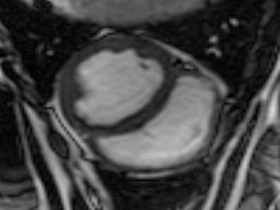

Easy-Trigger ist ein Medizinprodukt für die Herz- und Gefäßbildgebung in der Magnetresonanztomographie (MRT), das bifunktional bei Ungeborenen und Erwachsenen eingesetzt werden kann. Als weltweit erstes und einziges MRT-taugliches Doppler-Ultraschallgerät ermöglicht es erstmals Kombinationsuntersuchungen von MRT und Ultraschall. Der Ultraschallkopf wird auf dem Bauch oder über dem Herzen des Patienten platziert. Es ermöglicht erstmals die zeitliche Abstimmung der Herzaktion von ungeborenen Kindern mit dem MRT und damit MRT-Untersuchungen des kindlichen Herzens. Des Weiteren kann es zur Überwachung der Ungeborenen bei MRT-Untersuchungen von Schwangeren eingesetzt werden. Durch die Verwendung der Doppler-Ultraschall-Technik ist die Anwendung am Erwachsenen im Vergleich zum EKG robuster, einfacher und sogar bei höheren Feldstärken einsetzbar, bei denen das EKG nicht mehr zuverlässig arbeitet.

Cardiac MRI of the Fetal Heart Using a Novel Triggering Method: Initial Results in an Animal Model.

J Magn Reson Imaging. 2012 May;35(5):1071-6.